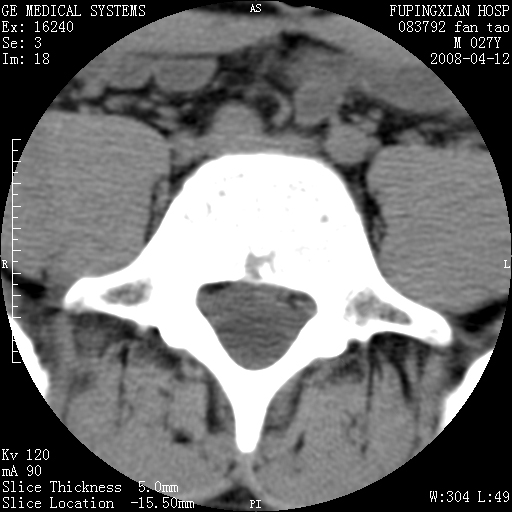

以下是引用前行在2008-4-13 13:53:00的发言:[br]椎间盘髓核终板下突出形成许莫氏结节及椎间盘突出,建议mr检查

以下是引用xclzq_910在2008-4-13 12:43:00的发言:[br]这个应该没什么了,椎间盘突出后反应性骨质吸收硬化.建议mr